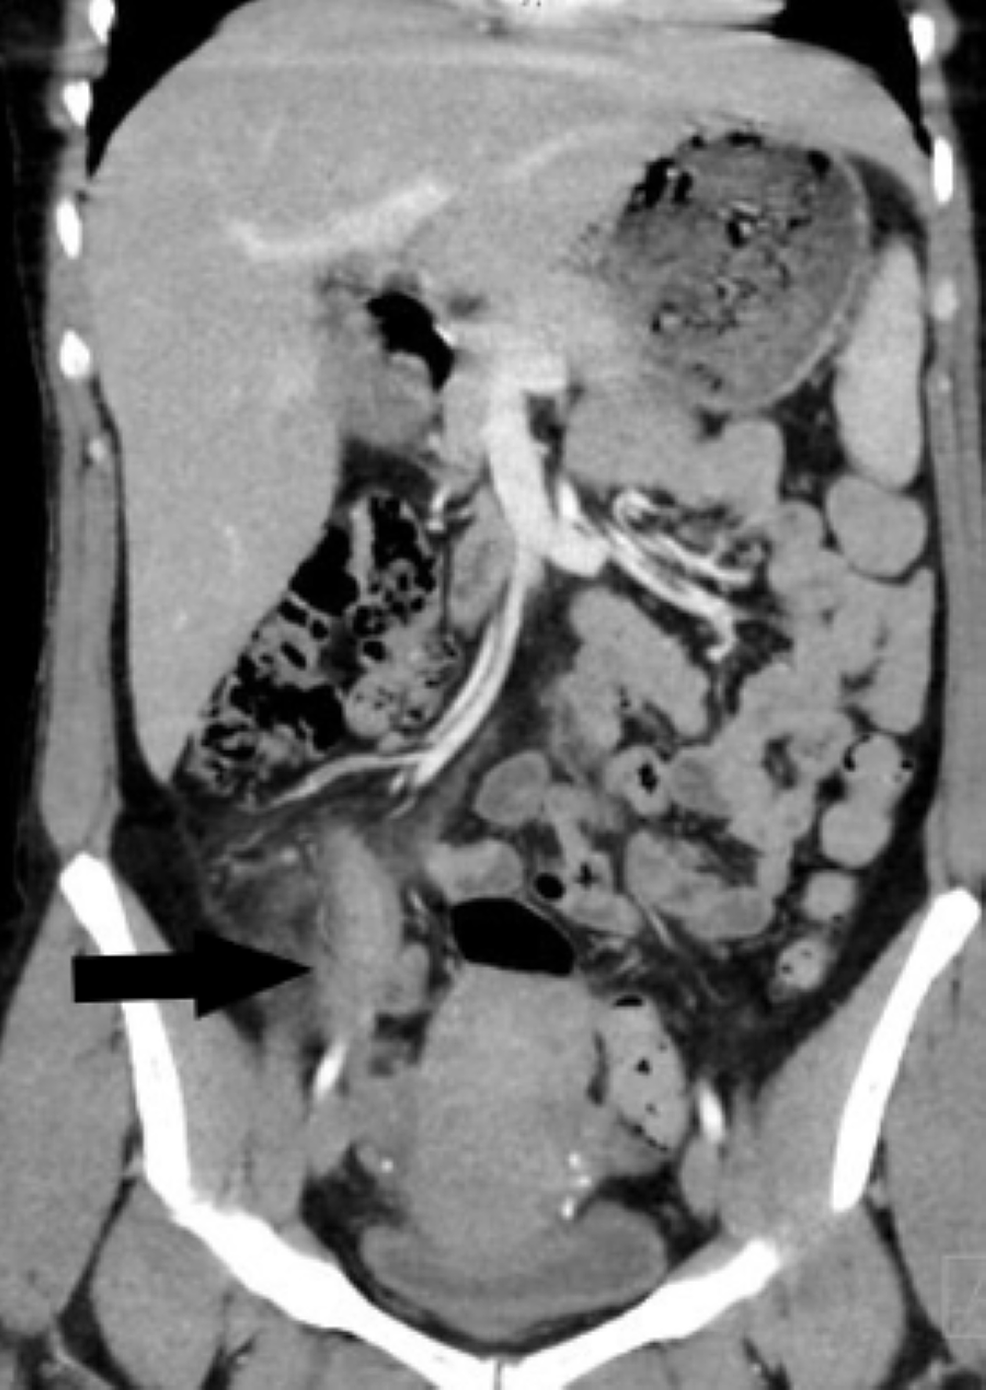

Cureus Accuracy of Computed Tomography in Differentiating Perforated Endo On Appendix acute appendicitis is the most common surgical diagnosis of abdominal pain in the right lower quadrant [1]. endometriosis of the appendix is uncommon. Its clinical presentation varies from asymptomatic to acute abdominal. endometriosis of the appendix (ea) has been identified in less than 1% of patients with pelvic endometriosis. sometimes it can even spread outside of. Endo On Appendix.

Appendicitis Caused by Endometriosis Within the Bowel Wall Cureus Endo On Appendix acute appendicitis is the most common surgical diagnosis of abdominal pain in the right lower quadrant [1]. In rare cases, endometriosis spreads to the appendix. endometriosis of the appendix (ea) has been identified in less than 1% of patients with pelvic endometriosis. Its clinical presentation varies from asymptomatic to acute abdominal. endometriosis of the appendix is uncommon.. Endo On Appendix.

Cureus Appendicitis Caused by Endometriosis Within the Bowel Wall Endo On Appendix endometriosis of the appendix (ea) has been identified in less than 1% of patients with pelvic endometriosis. acute appendicitis is the most common surgical diagnosis of abdominal pain in the right lower quadrant [1]. sometimes it can even spread outside of the stomach or abdomen. In rare cases, endometriosis spreads to the appendix. Its clinical presentation varies. Endo On Appendix.